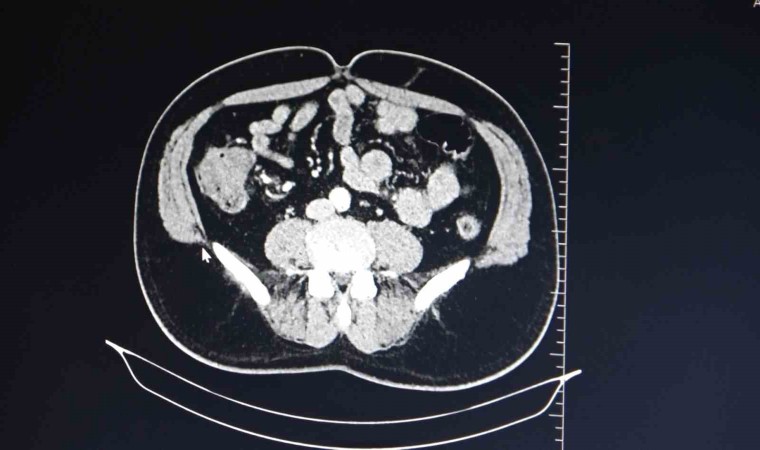

Hastaların kolon kanserine yakalanmaması açısından günlük yaşamda uzun süreler hareketsiz kalmamaları ve yedikleri yemeklere dikkat etmesinin önem arz ettiğini belirten Dr. Öner, "Aile bireylerinde kolon kanseri teşhisi olan insanlarında dikkat etmesi gerekiyor. Kolon kanseri, kalın bağırsakta anormal kötü hücrenin çoğalması, bunun sonucunda kalın bağırsağı tam tıkaması ve kalın bağırsak tıkanıklığıyla hastanemize başvuran hasta gruplarıdır. Kolon kanseri için risk faktörlerine baktığımızda, hareketsiz yaşam, çok yağlı ve etli yemeklerin tüketilmesi nedenleri sayılabilmektedir" dedi.

Bunun dışında ailesel yani genetik olarak kanser vakaları bulunmakta olduğunu aktaran Dr. Öner, "Aile bireylerinde kolon kanseri teşhisi konulan hastalarda, aile bireyinin tanı konulduğu yaştan itibaren 10 sene geriye gidilerek hastanın tarama grubuna girmeleri gerekmektedir. Kolon kanseri şikayetleri karın şişliği, büyük abdesti rahat yapamama, büyük abdest yerinde kanama gibi şikayetlerdir. Kolon kanserine erken tanı koyulması halinde şifa ile sonuçlanabilecek küratif olarak sonuçlanmaktadır. İleri evrede kolon kanseri alan hastalarda ise medikal onkoloji takibine girip, kemoradyoterapi işlemlerine maruziyetleri olabilmektedir" diye konuştu.

Kolon kanseri hastalarının ameliyatla kurtulabileceğini ve 40 yaşından sonra kontrollerin aksatılmamasının önemli olduğunu vurgulayan Dr. Öner, "Kolon kanserinin oluşmaması için özellikle hareketsiz yaşamdan hareketli yaşama dönülmesi, sebze ve meyvenin sık tüketilmesi, etli ve yağlı yemeklerin en fazla haftada 1-2 defa tüketilmesi gerekmektedir. Kolon kanseri ameliyatlarında ise kitlenin tuttuğu alanı besleyen ana damarlarla beraber alındığı zaman hastalar şifa buluyor. Dünyada kolon kanseri tarama yaş grupları olarak 40 yaşından itibaren yılda bir defa olmak üzere büyük abdest yerinden gaitada gizli kana bakılması, 50 yaşından itibaren ise 10 senede bir olmak üzere büyük abdestten kamera ile bakılması önem arz etmektedir" şeklinde konuştu.